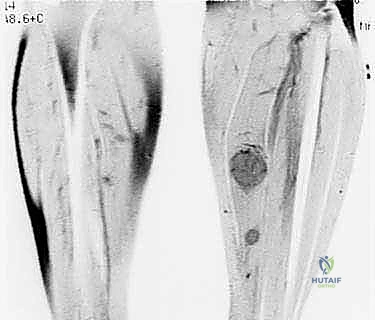

* الكسور المرضية: حدوث كسر في العظم نتيجة إصابة طفيفة جداً لا تسبب كسراً في العظم السليم، مما يدل على ضعف العظم بسبب ورم.

- الأشعة السينية (X-ray): الخطوة الأولى لتقييم العظام وتحديد نمط التدمير العظمي.

- الأشعة المقطعية (CT Scan): ضرورية لتقييم القشرة العظمية والتكلسات داخل الورم، وللبحث عن أي انتشار في الرئتين.